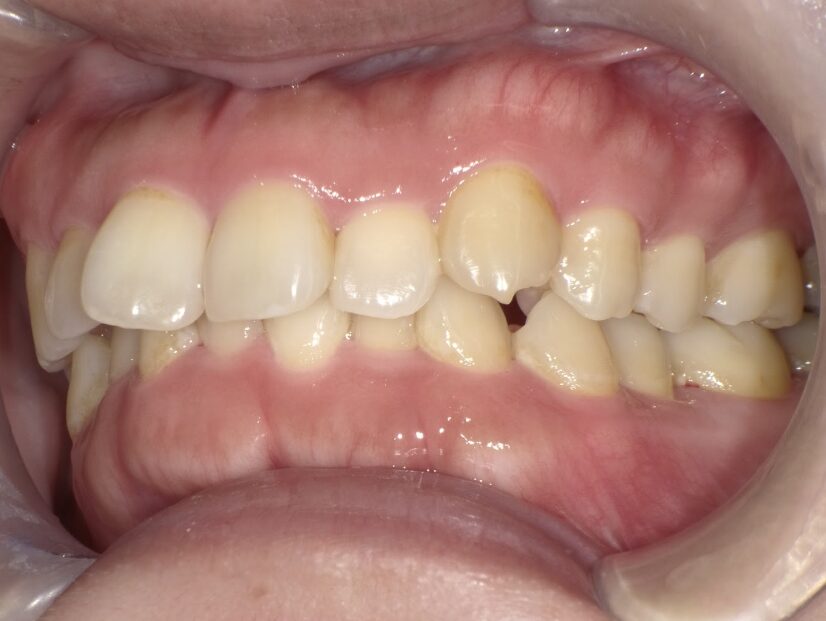

過蓋咬合

ガタガタを主訴に当院を受診され、上下前歯部に叢生(ガタガタ)と過蓋咬合(上の歯が下の歯を深く覆いかぶさっている状態)を認めました。

IPRを使用してマウスピース型矯正装置(インビザライン)を使用し過蓋咬合及び叢生の改善を行いました。

年齢/性別30代女性

抜歯部位非抜歯

治療期間1年6ヶ月